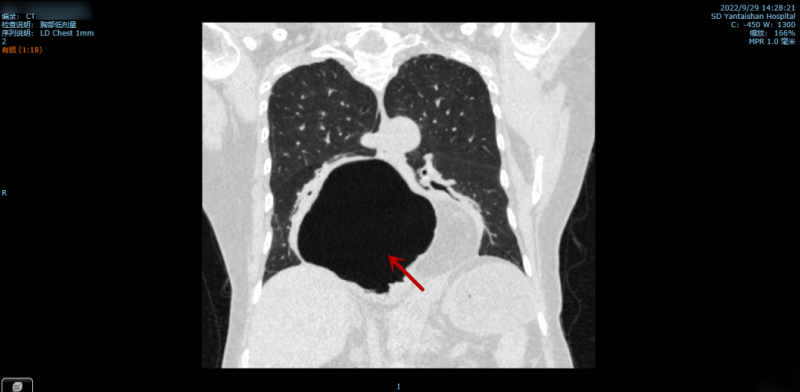

图中所示,该患者的胃“跑”到了膈肌以上。

据悉,该患者今年58岁,4年前的一次外伤导致其食管裂孔撕裂,胃组织疝进入到胸腔内。4年间反复出现腹痛、反酸以及烧心等症状,最初每月出现一次,到后来发展到每周一次,每三天一次,患者痛苦不堪,也曾辗转到多地就医,均以其疝囊较大而未得到有效治疗。半个月前,症状加重,患者因剧烈腹痛而到烟台山医院就诊。